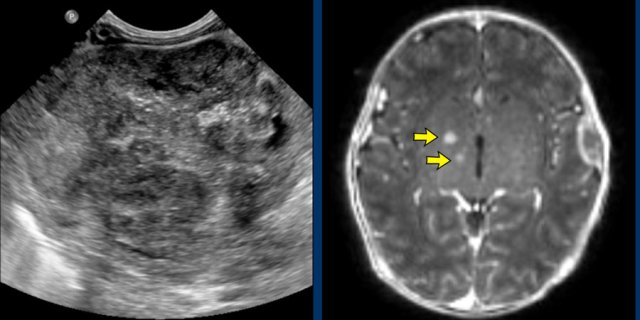

Malignant rhabdoid tumor of the kidney

Malignant rhabdoid tumor of the kidney with brain (arrows) and bone metastases Malignant rhabdoid tumor of the kidney with brain (arrows) and bone metastases

Images

Two-week-old girl presenting with a mass in the left kidney.

A MRI of the brain at the time of initial diagnosis showed tiny lesions, possibly metastases (arrows).

An MRI four weeks later showed multiple brain and skull metastases.

The patient died two weeks later.